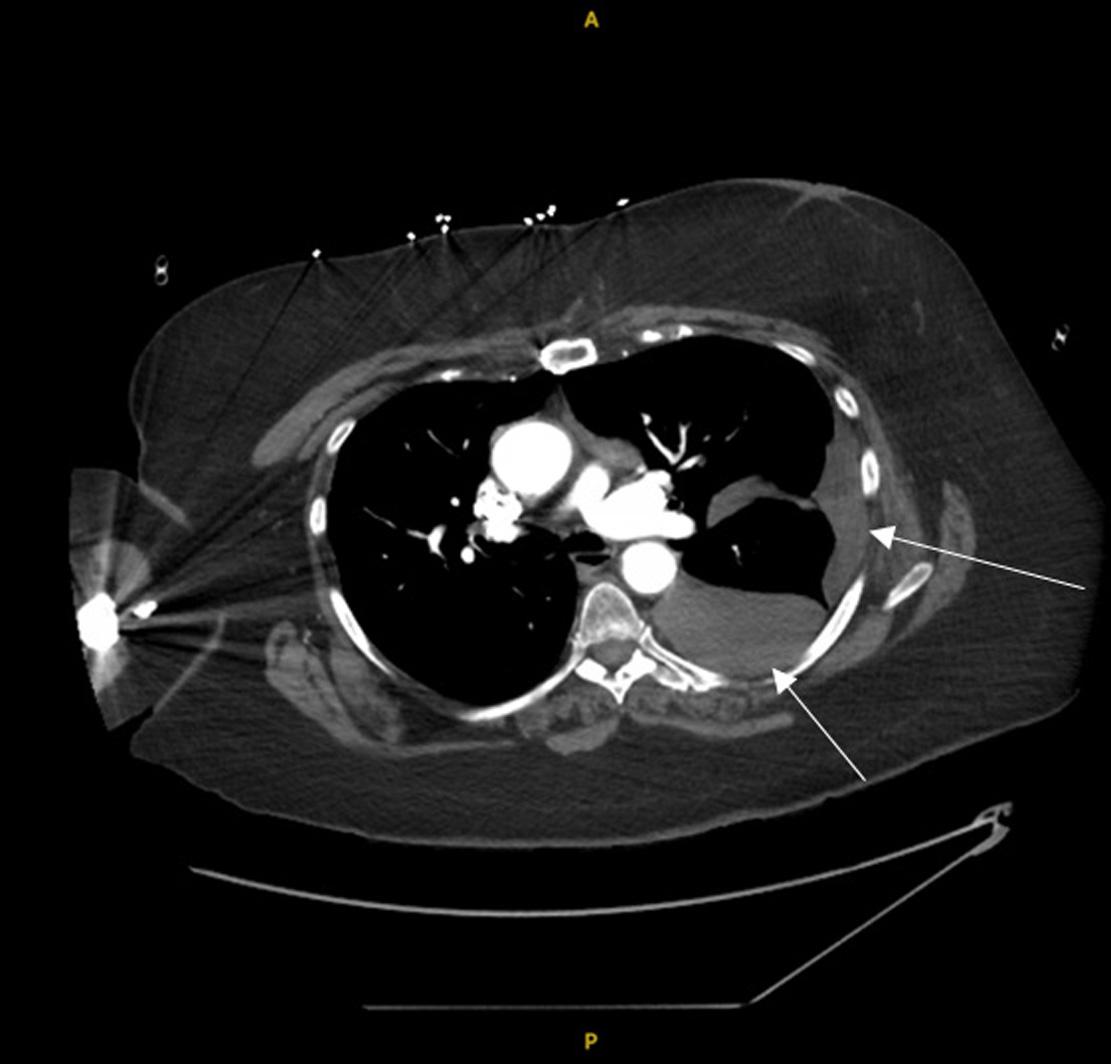

Emergentcomputedtomographyoftheabdomenand pelvisrevealedalargeleftretroperitonealandperitoneal hematomasecondarytoleftRAArupture,aswellasconcern fordevelopingsplenicinfarctsintheleftlowerrenalpole (Image).Thepatientwastakenemergentlytotheoperating room(OR)forexploratorylaparotomywithintwohoursof EDarrival.Sheunderwentsuprarenalcross-clampingwith repairoftheleftrenalarteryandligationofrenalvessels.She returnedtotheORtwodayslaterforleftnephrectomyand abdominalclosure.Shewasextubatedandtransferredtothe floor.Shewasdischargedhometwodayslaterin goodcondition.